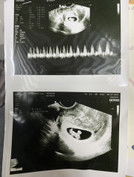

แม่ๆไปซาวด์เห้นน้องกันตอนกี่เดือนค่ะแม่ๆ ทางนี้ท้อง7+3หมอให้ไปซาวด์แต่ยังไม่เจอน้องเลย แอบกังวล กลัวว่าอีก2อาทิตย์ไปซาวด์อีกจะไม่เจอน้องจัง #ขอคำแนะคำปรึกษาคะ

เราซาวผ่านช่องคลอดเจอตอน6วีค5วันค่ะแม่ แต่ว่าร่างกายแม่แต่ละคนไม่เหมือนกัน บางคนเจอช่วง10-13สัปดาห์เลยค่ะ เป็นกำลังใจให้นะคะคุณแม่

อย่าคิดเยอะไปนะคะแม่ บ้านนี้เจอน้องตอน 11 วีคเลยค่ะ ซาวด์ผ่านหน้าท้องไม่เจอ ต้องซาวด์ผ่านช่องคลอดค่ะ อย่าคิดเยอะนะคะแม่

ทางนี้ซาวเจอถุงตอน 8w ค่ะ และเจอตัวน้องตอน 10w เลย แต่ละคนไม่เหมือนกัน เราซาวผ่านช่องคลอดทุก2วีคกว่าจะเจอ ลุ้นมากค่ะ

บ้านนี้เห็นตอน10สัปดาห์ค่ะไปซาวรอบแรกที่6-7สัปดาห์แล้วไม่เห็นตัวเหมือนกันค่ะแต่มีถุงการตั้งครรภ์กับถุงไข่แดงค่ะ

บ้านนี้เจอน้องตอนอายุครรภ์ 10-11 สัปดาห์ค่ะ ไม่ต้องกังวล น้องยังตัวเล็กอยู่อาจจะยังไม่ชัดเท่าไหร่

เจอถุงตั้งครรภ์และถุงไข่แดงตอน 6วีค พอ 8วีค เจอน้องพร้อมหัวใจค่ะ

8วีคค่ะ ซาวด์ผ่านช่องคลอดเพราะอายุครรภ์ยังน้อยมากๆ

ไปฝากตอน 8 วีคแล้วนึกว่าจะไม่เจอ แต่เจอแล้วงับ

บ้านนี้ซาวด์เจอตัวน้องตั้งแต่8วีคเลยค่ะ